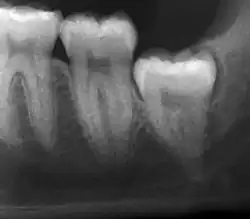

Impacted wisdom teeth are classified by their direction of impaction, their depth compared to the biting surface of adjacent teeth and the amount of the tooth's crown that extends through gum tissue or bone. Impacted wisdom teeth can also be classified by the presence or absence of symptoms and disease. Screening for the presence of wisdom teeth often begins in late adolescence when a partially developed tooth may become impacted. Screening commonly includes a clinical examination as well as x-rays such as panoramic radiographs.

Diagnosis

The diagnosis of impaction can be made clinically if enough of the wisdom tooth is visible to determine its angulation, depth, and if the patient is old enough that further eruption or uprighting is unlikely. Wisdom teeth continue to move to the age of 25 years old due to eruption, and then continue some later movement owing to periodontal disease.[18]

If the tooth cannot be assessed with clinical exam alone, the diagnosis is made using either a panoramic radiograph or cone-beam CT. Where unerupted wisdom teeth still have eruption potential several predictors are used to determine the chance of the teeth becoming impacted. The ratio of space between the tooth crown length and the amount of space available, the angle of the teeth compared to the other teeth are the two most commonly used predictors, with the space ratio being the most accurate. Despite the capacity for movement into early adulthood, the likelihood that the tooth will become impacted can be predicted when the ratio of space available to the length of the crown of the tooth is under 1.[5]: 141